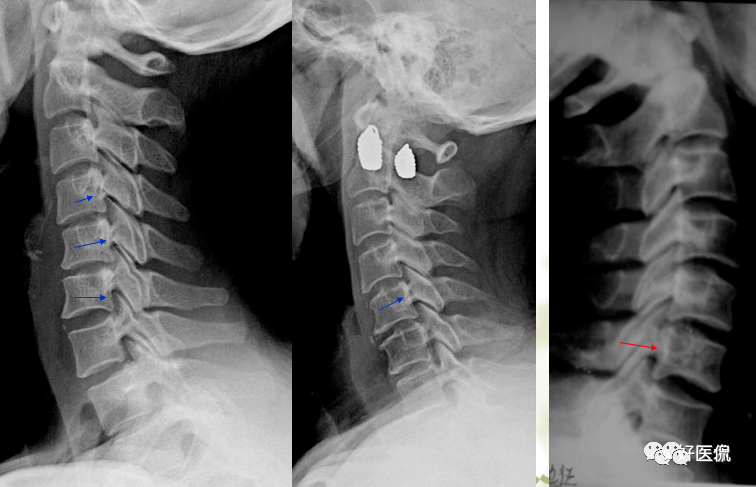

双边双突征

椎体旋转所致双边征双侧椎弓根形状不对称,钩椎关节间隙及椎弓关节